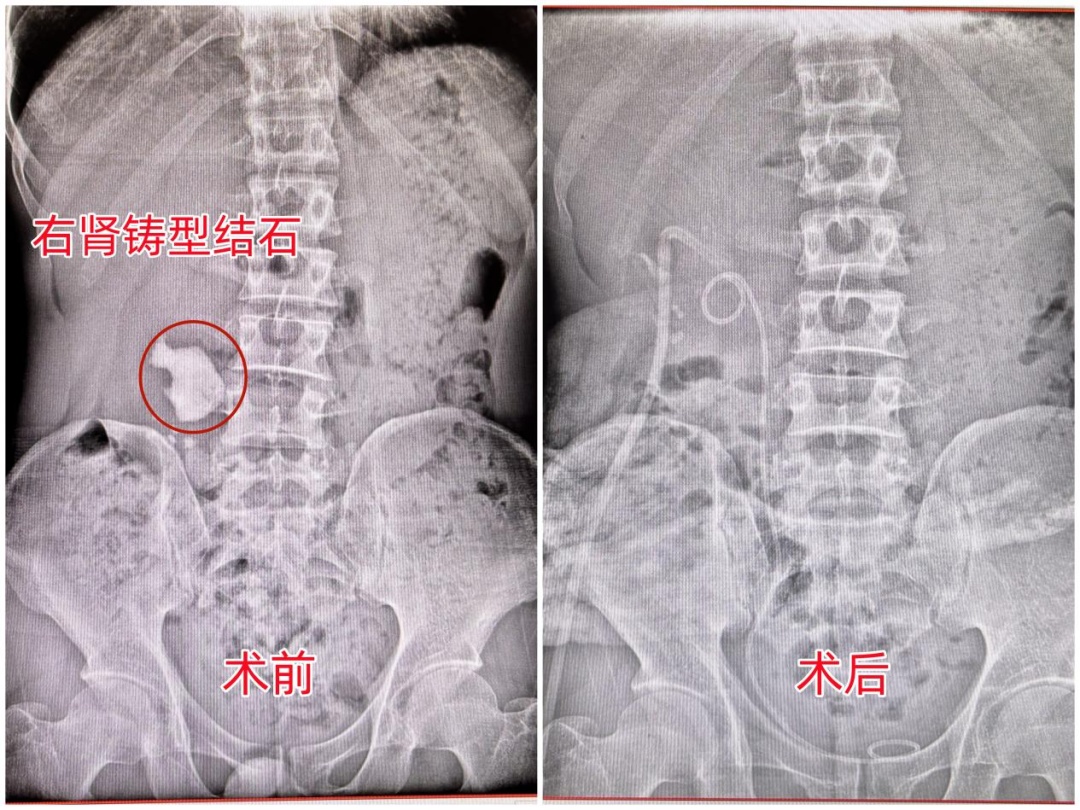

刘先生术前术后腹平片对比图

经详细检查,医生确诊刘先生患有右肾铸型结石并右肾积水,且结石最长径达5.7厘米,手术指征明显。

“从患者术前的CT上可以看到,从右肾的上盏、中盏再到下盏,基本上都被结石给填满了。由于结石会不断刺激肾脏黏膜,如果不及时治疗,可能会引发出血、感染,引起肾绞痛等。”长沙京石医院泌尿外科副主任张贻骅表示。

结合刘先生的基本情况和病情特点,张贻骅立即为他制定了双镜联合超微创取石手术方案。“手术很顺利,由于患者右肾铸型结石体积大且质硬,我们通过穿刺建立了取石通道,同时再联合输尿管软镜进行取石,定位结石后使用钬激光将铸型结石击碎,成功将所有碎石洗出体外,全程仅用时70分钟,一次手术就将这枚巨石取出体外,成功化解了这次危机。”